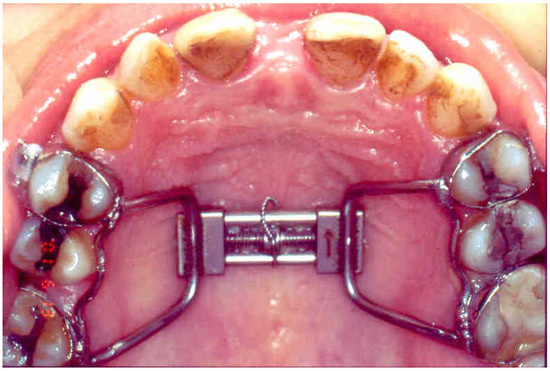

2.2. Surgical Procedure